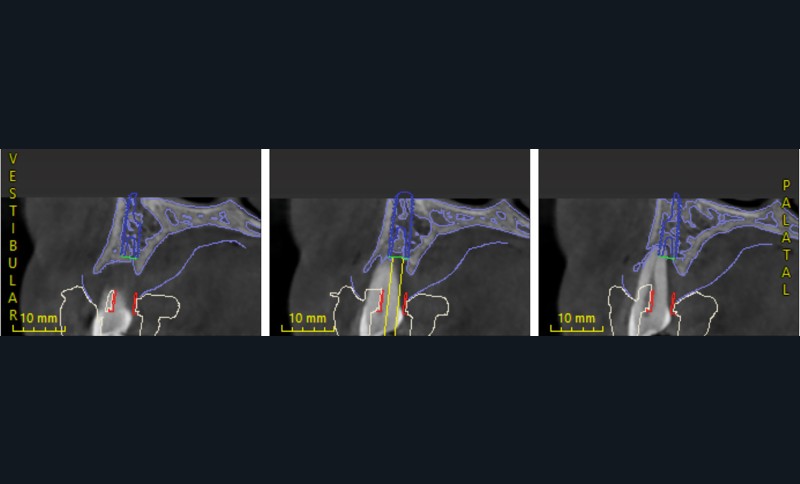

L’empreinte optique, les photographies et le CBCT ont permis une fusion précise des données numériques pour planifier les axes et positions implantaires en fonction du projet prothétique final (fig. 3, 4).

Cette planification a ainsi intégré la future ligne d’émergence et la gestion anticipée des tissus mous [2].